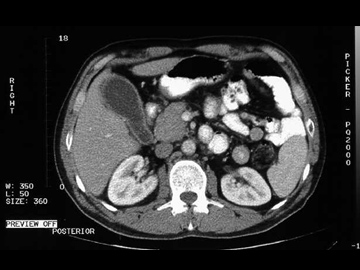

TAC de abdomen